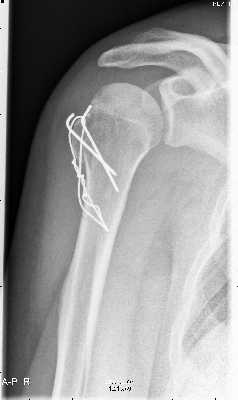

Maar op 9 augustus bleek dan niet zo te zijn en moest er de volgende dag geopereerd worden. |

| na de operatie was alles weer vast gezet. |